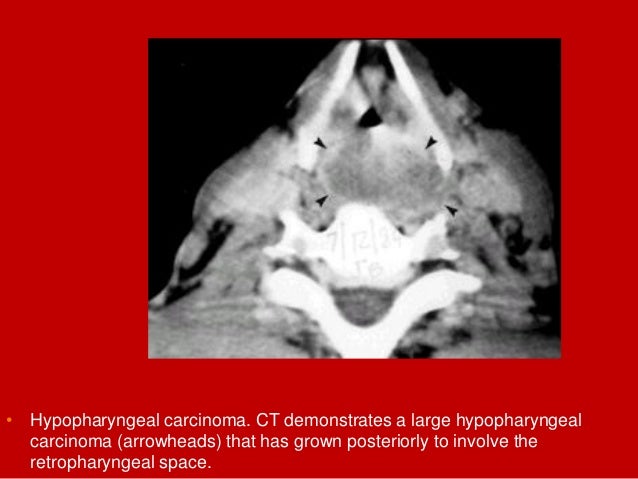

70. 70. • Hypopharyngeal carcinoma. CT demonstrates a large hypopharyngeal carcinoma (arrowheads) that has grown posteriorly to involve the retropharyngeal space.